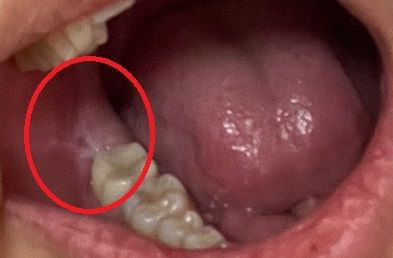

그러다가 어느순간에 불안감이 느껴지는지 추적하다가 입안에 볼이 잇몸에 팽팽하게 묶여 엄청난 장력을 윗방향으로 받고 있는 걸 발견했습니다. 살이 너무 하얗고 팽팽해 제가 중간을 손으로 뜯자 사진처럼 되었고, 장력이 좀 풀리자 모든 증상이 훨씬 나아져서 이곳이 문제라는 걸 알게되었습니다. 특히 웃을 때 저 볼쪽 살이 마지막 윗어금니에 찝힌다?쓸려서 제가 굉장히 불편해하는 것이었습니다.

사진상의 연조직은 정상으로 보이나 위에 치아가 아래 잇몸을 자극한다면 불편감이 들수 있기 때문에 경우에 따라서는 반대쪽 치아의 날카로운 부분을 삭제 해주는 경우도 있습니다.